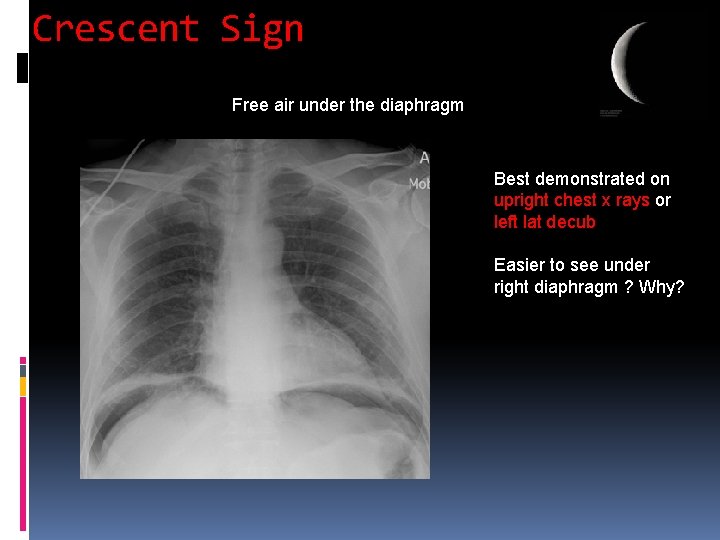

Crescent Sign Free air under the diaphragm Best demonstrated on upright chest x rays or left lat decub Easier to see under right diaphragm ? Why?